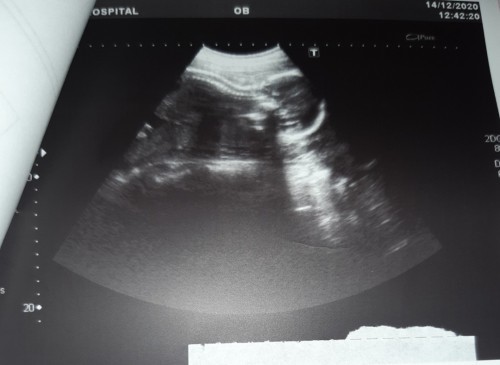

ตอนนี้อายุครรภ์ 22 สัปดาห์ ได้ไปหาหมอ 2 ที่ หมอที่ 1 บอก ลูกปกติดี หมอที่ 2 บอก ลูกตัวเล็กมาก อายุครรภ์เท่านี้ เด็กต้องน้ำหนัก 800-900 กรัม ลูกเรา 455กรัม อยากทราบแม่ท่านอื่นอายุครรภ์เท่ากันลูกน้ำหนักเท่าไรแล้วค่ะ หมอว่าไงบ้าง

อายุครรภ์ตอนนี้22สัปดาห์ค่ะ ช่วงหมอนัดอายุครรภ์21สัปดาห์น้ำหนักน้องได้392กรัม หมอบอกน้ำหนักตามเกณฑ์ นะค่ะ